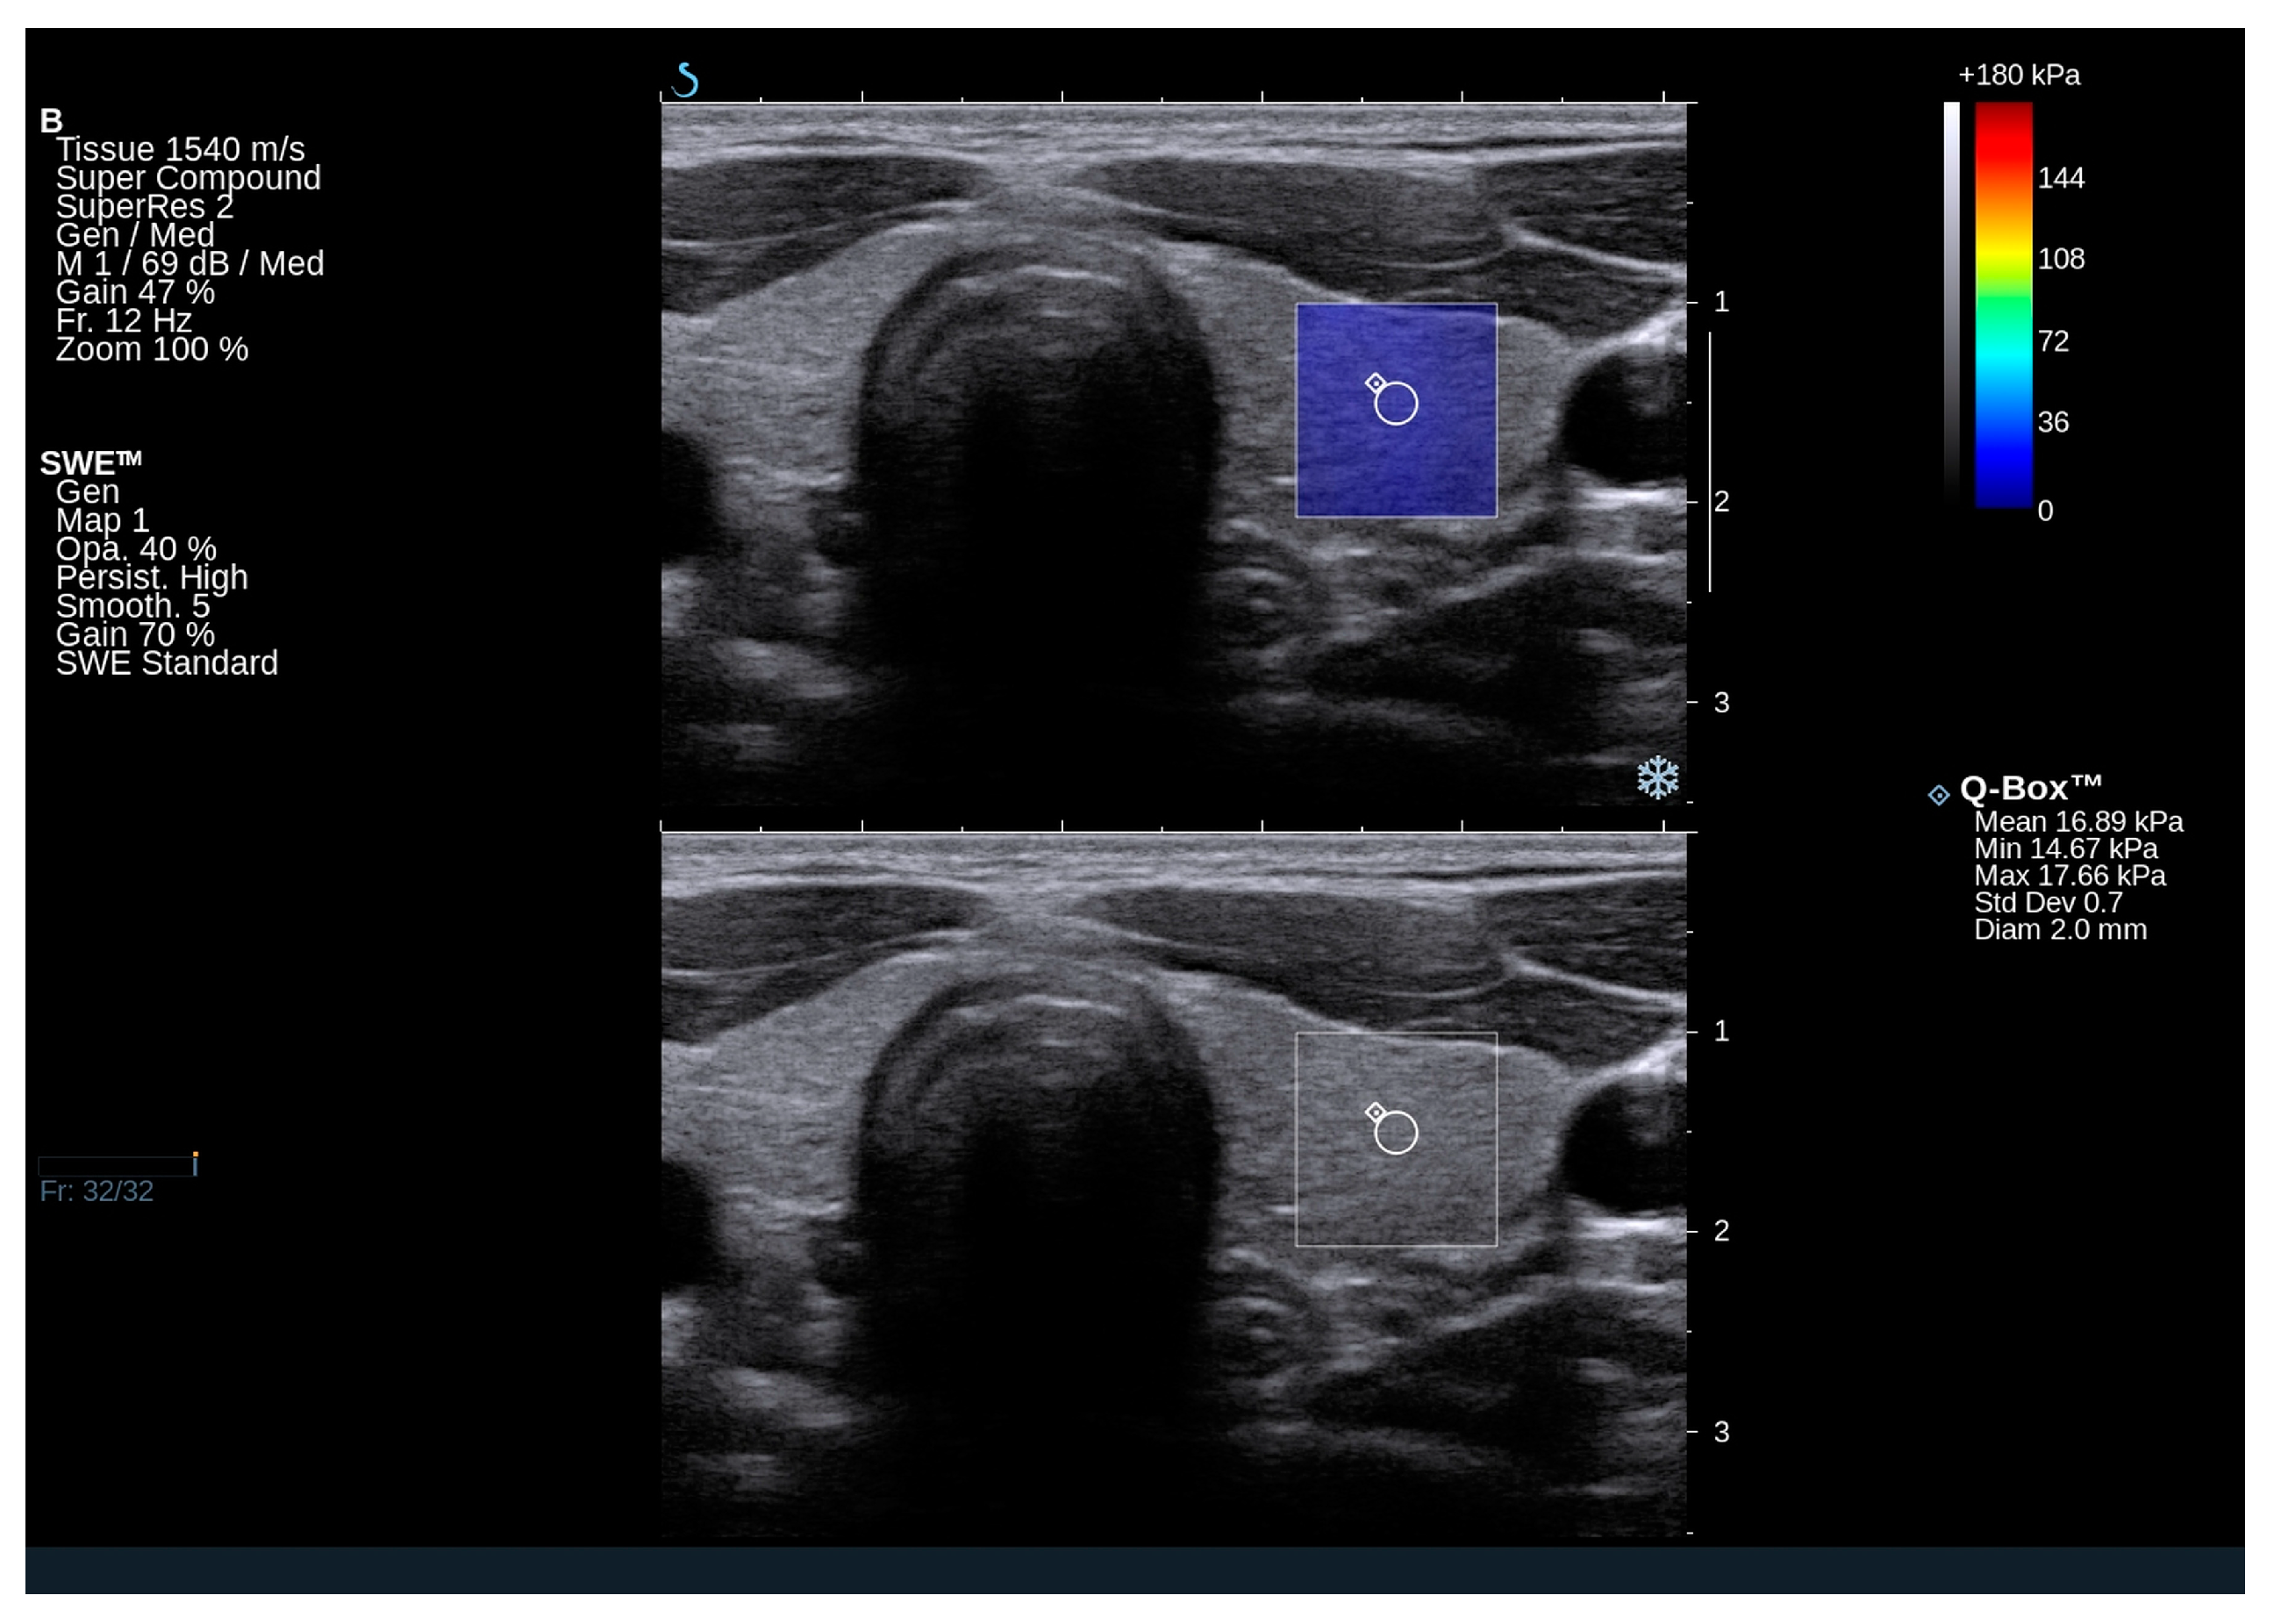

2.3. Elastography Results

4.2. Thyroid Ultrasound and Shear Wave Elastography (SWE)

| Right lobe Qbox mean (kPa) | 17.2 (11.9–20.9) | |

| Right lobe Qbox min (kPa) | 11.3 (6.8–13.3) | |

| Right lobe Qbox max (kPa) | 25.4 (18.8–31.5) | |

| Right SD | 3.5 (2.7–4.5) | |

| Left lobe Qbox mean (kPa) | 14.9 (11.3–21.5) | |

| Left lobe Qbox min (kPa) | 8.7 (5.3–12.5) | |

| Left lobe Qbox max (kPa) | 22.9 (17.3–29.6) | |

| Left SD | 3.2 (2.1–4.0) | |